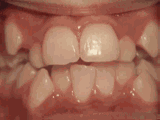

第四种: 牙列拥挤,牙槽骨过窄,就没有足够空间,只好前后左右高低上下乱长,经过矫后的牙是这样的。